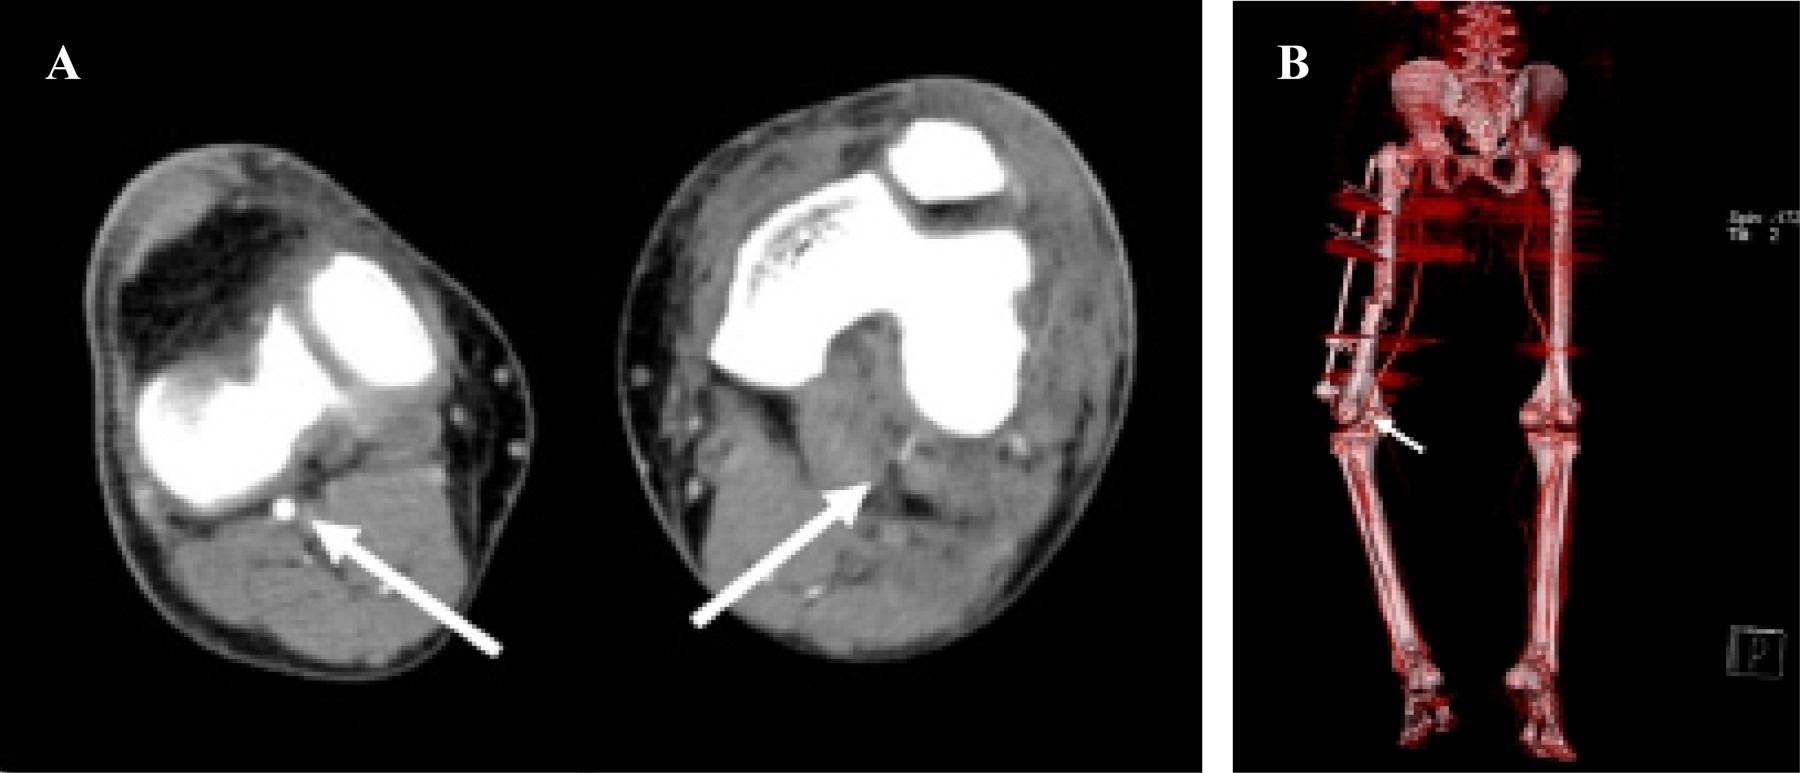

La angiotomografía (Figura 7) es una alternativa a la angiografía que permite evaluar tanto el componente vascular como óseo en este tipo de lesiones y la cual se ha popularizado en los últimos años. Entre sus ventajas destacan: tener mayor disponibilidad en los centros de trauma, menor radiación e incluso menores costos.69,70

La sensibilidad y especificidad reportadas en la mayoría de los estudios que evalúan lesiones vasculares en trauma de miembros inferiores han mostrado valores similares a la angiografía.71 En un estudio de 63 pacientes, Inaba y colegas72 observaron que la angiotomografía fue diagnóstica en 62 de los casos y no diagnóstica en uno de los casos por presencia de artefactos (fragmentos de proyectil) que no permitían evaluar adecuadamente la imagen, 22 imágenes fueron positivas para lesión vascular, a 19 de éstas se les hizo manejo quirúrgico. En los 40 estudios con reporte negativo para lesión vascular se logró seguimiento en 90% de los casos sin evidencia de signos clínicos de lesión vascular, registrando al final del estudio una sensibilidad y especificidad de 100%.

En un estudio más reciente Rieger y colaboradores73 evaluaron la angiotomografía para el diagnóstico de lesiones vasculares en miembros superiores e inferiores en contexto de politrauma, encontrando una sensibilidad, especificidad y precisión de 95, 87 y 93% respectivamente. Los autores consideraron a ésta la primera ayuda imagenológica de elección en el contexto de politrauma al poder evaluar al mismo tiempo el componente óseo y vascular, incluso de vasos de pequeño calibre.

Figura 7